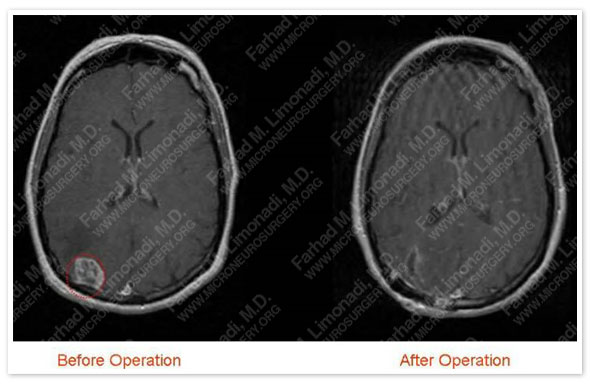

Post-op Imaging

Postoperative MRI showed complete resection of the radiographically apparent tumor. Tumor is outlined in a red dotted circle.